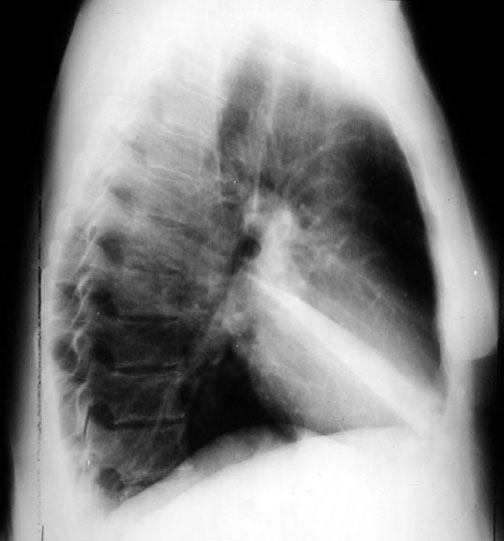

RML Atelectasis

• Vague density in right lower lung field (almost a normal film).

• Dramatic RML atelectasis in lateral view, not evident in PA view. Movement of transverse fissure.